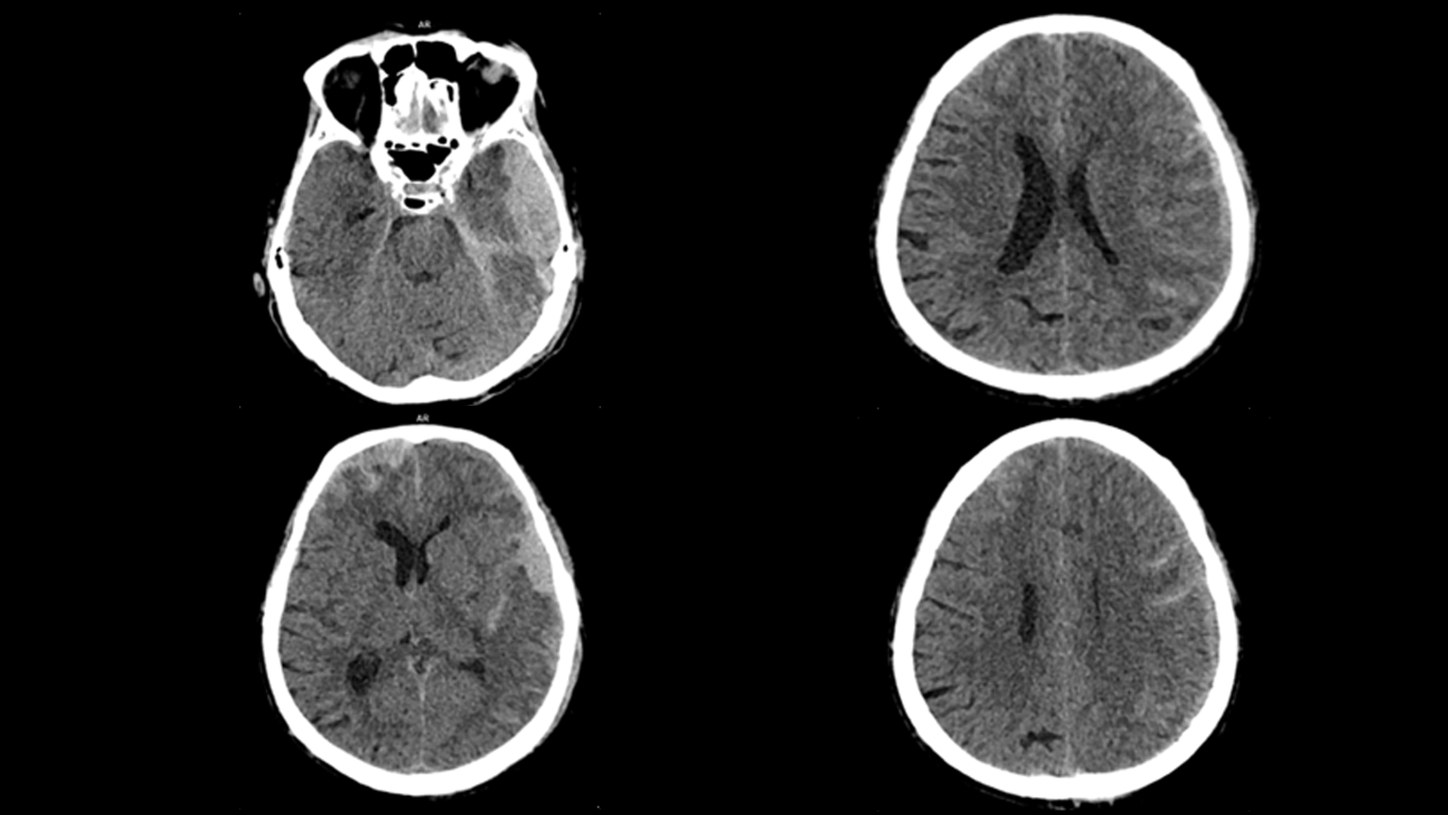

Whether portable in the Intensive Care Unit, or mobile in the ambulance as a Mobile Stroke Unit, SOMATOM On.site is designed to bring critical care imaging to your patients. With the first-of-its-kind telescopic gantry design, integrated positioning accessories, and proven SOMATOM technologies, you can achieve fast and reliable CT head imaging.

Proven SOMATOM technologies such as Stellar detector, iMAR, and ADMIRE® provide high image quality, enabling faster clinical decisions for critical care patients.

Evidence